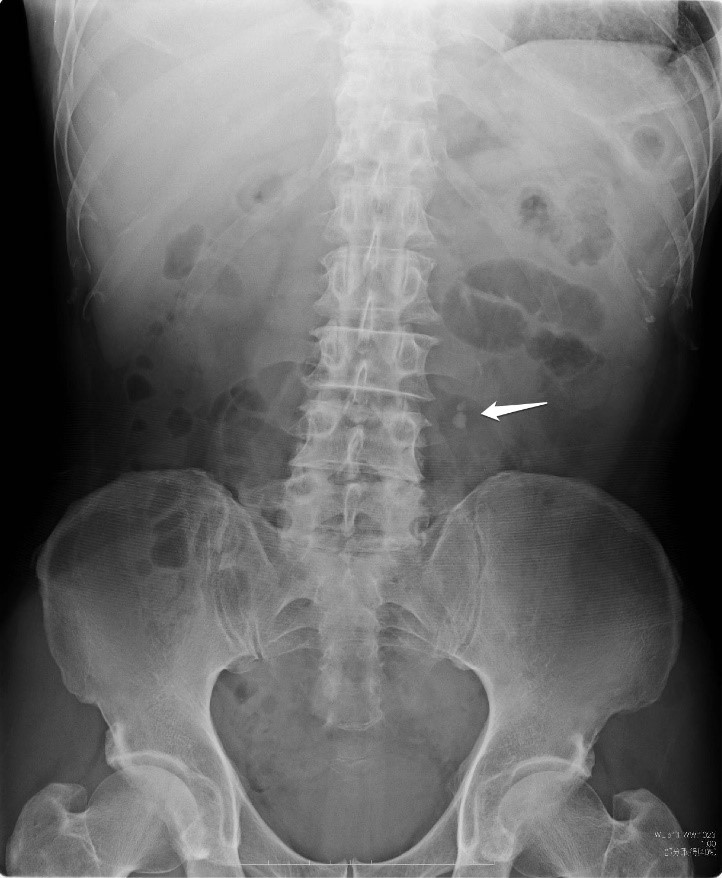

■ 腹部レントゲン(KUB)

腹部の炎症や異常ガスの有無などを見ますが、当院では特に腎臓や膀胱の位置確認、結石の有無を見ます。